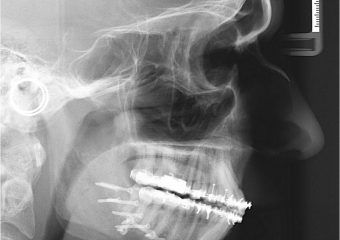

Telerradiografia após a cirurgia